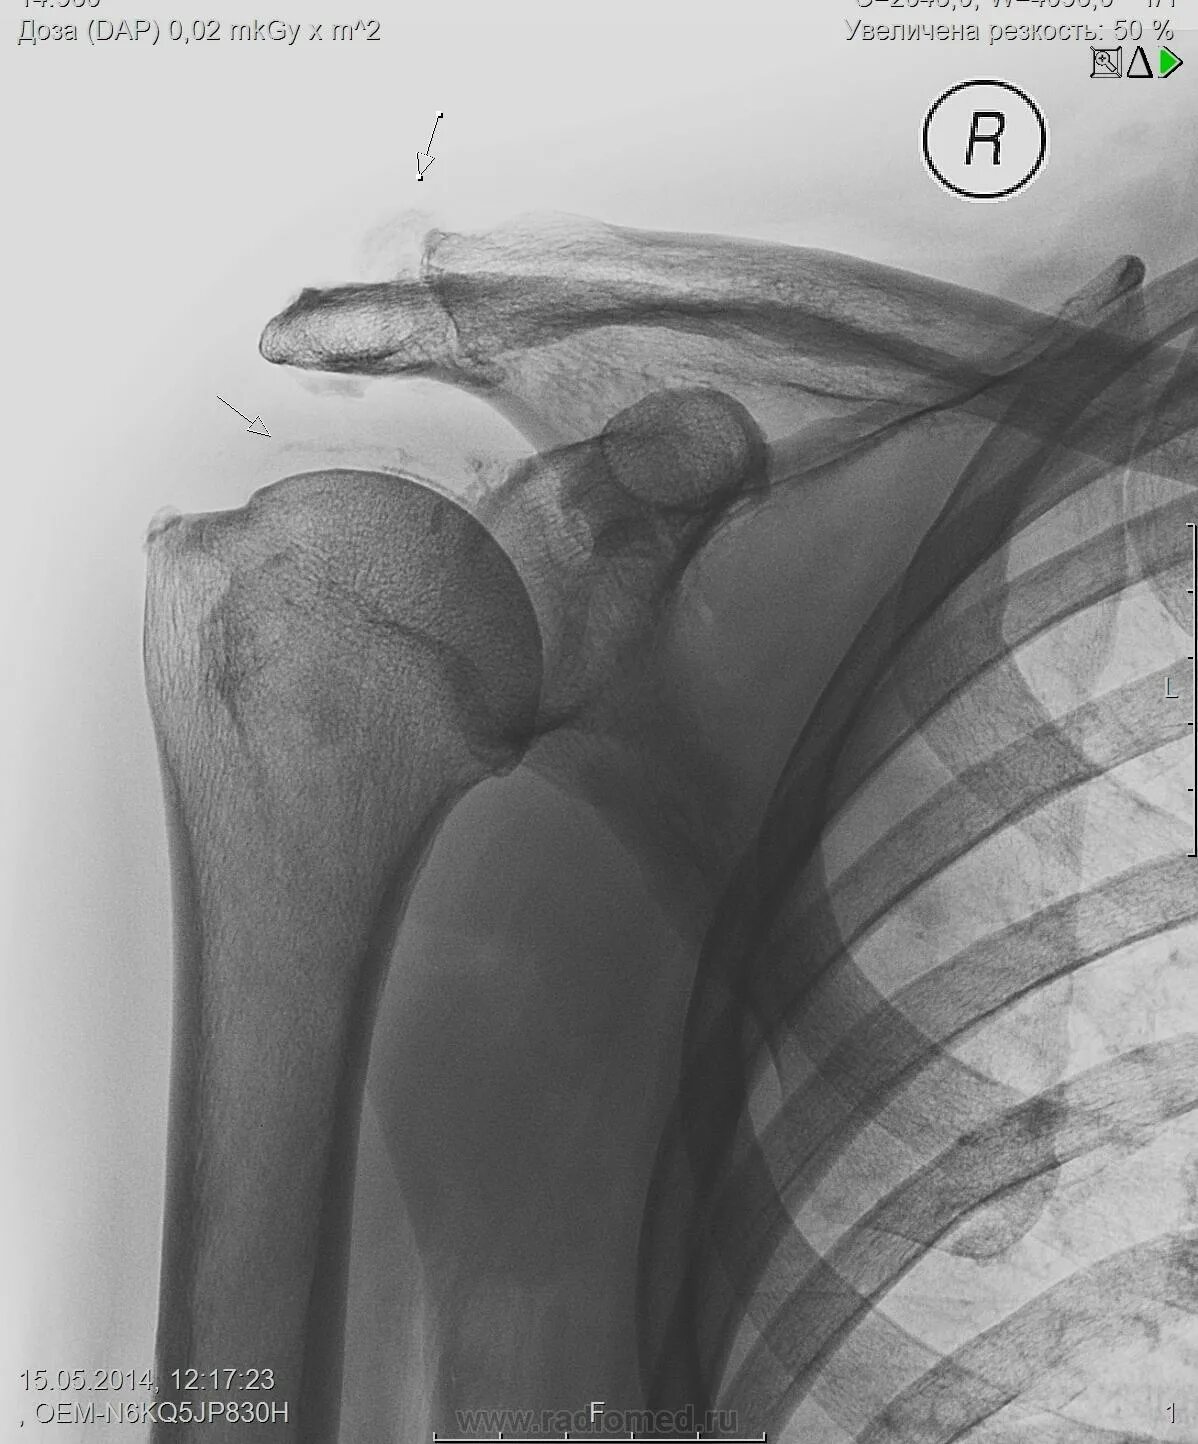

Обызвествление места прикрепления сухожилия